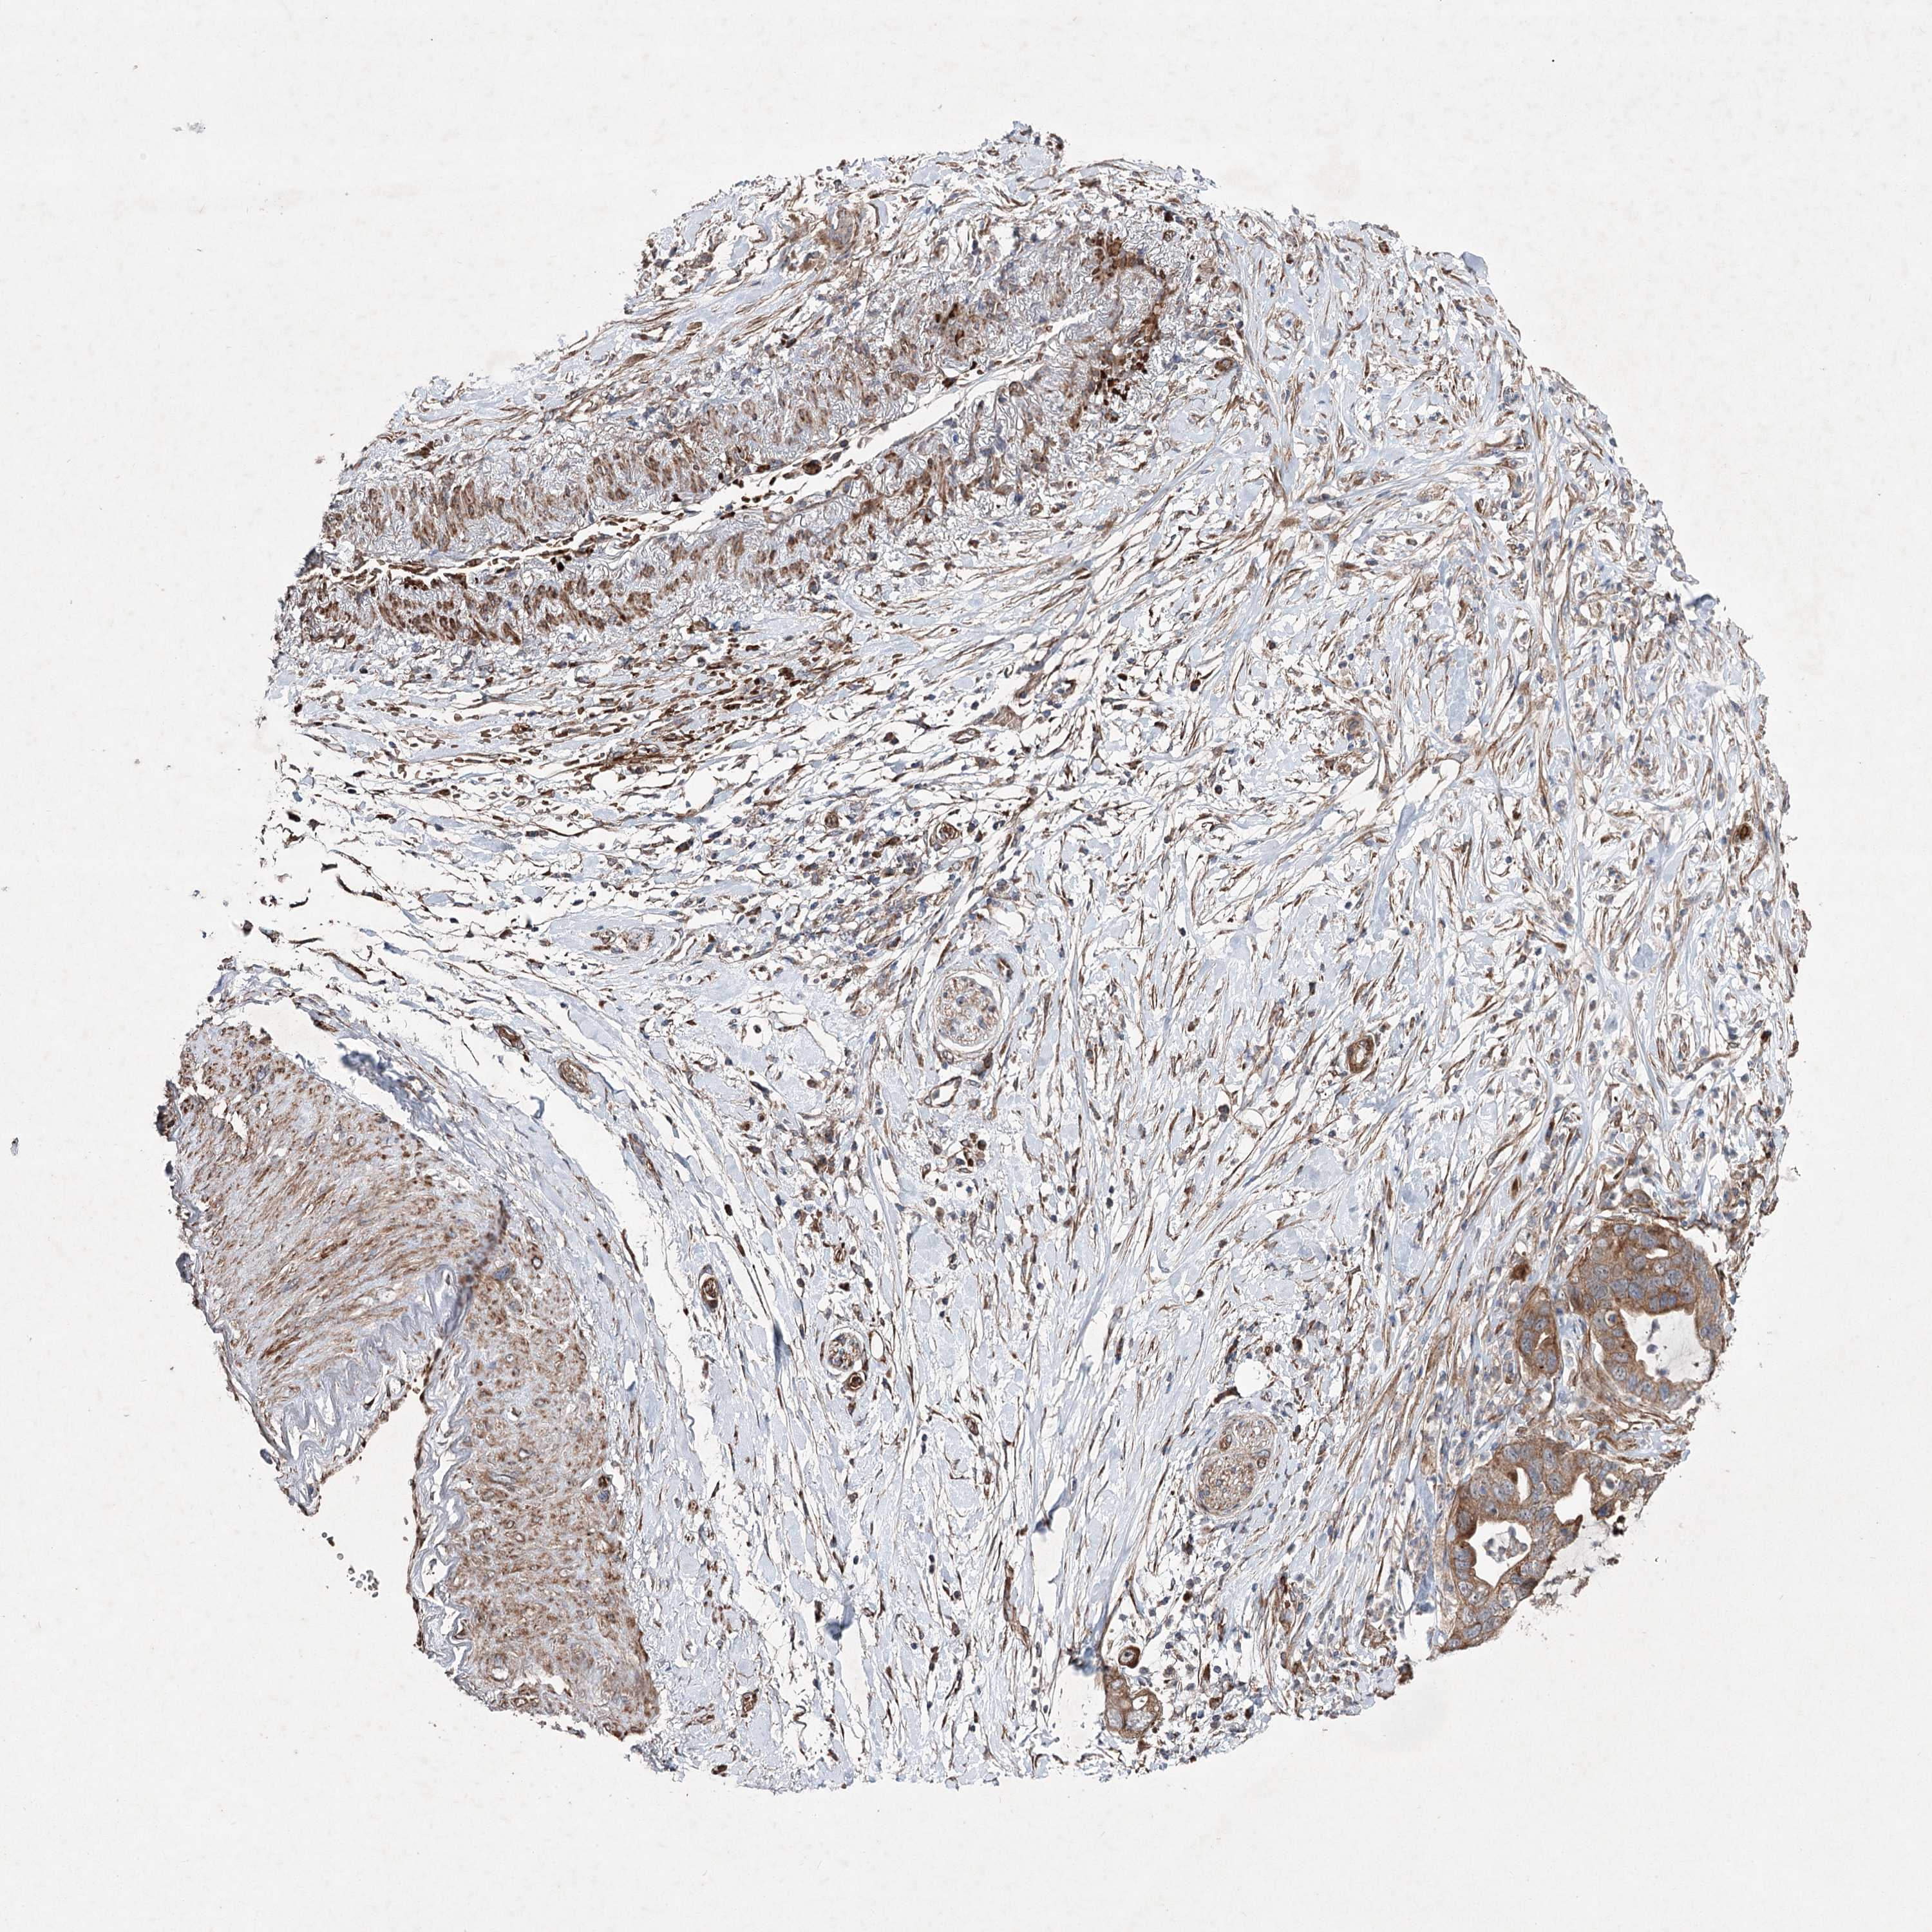

PANCREATIC CANCER - Protein expressioni

A mouse-over function shows sample information and annotation data. Click on an image to view it in a full screen mode. Samples can be filtered based on level of antibody staining by selecting one or several of the following categories: high, medium, low and not detected. The assay and annotation is described here.

Note that samples used for immunohistochemistry by the Human Protein Atlas do not correspond to samples in the TCGA dataset.

Antibody stainingi

Antibody staining in the annotated cell types in the current human tissue is reported as not detected, low, medium, or high, based on conventional immunohistochemistry profiling in selected tissues. This score is based on the combination of the staining intensity and fraction of stained cells.

Each image is clickable and will lead to virtual microscopy that enables deeper exploration of all samples and also displays staining intensity scores, fraction scores and subcellular localization as well as patient and tissue information for each sample.

Antibody HPA037898

Antibody HPA037899

Staining

High

Medium

Low

Not detected

Intensity

Strong

Moderate

Weak

Negative

Quantity

>75%

75%-25%

<25%

None

Location

Nuclear

Cytoplasmic/membranous

Cytoplasmic/membranous,nuclear

Adenocarcinoma, NOS